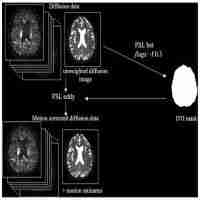

| Abstract | Diffusion tensor imaging (DTI) of the human optic nerve presents challenges from geometric distortion in echo planar imaging (EPI) caused by magnetic field inhomogeneity and partial volume artifacts caused by confounding signals from surrounding fat and cerebrospinal fluid (CSF). A protocol for human optic nerve DTI was developed with geometric distortion correction and suppression of fat and CSF signals. This protocol was modified from a conventional DTI protocol to acquire images and field maps covering the whole brain including contiguous slices of the optic nerves. The technique was applied to healthy volunteers and multiple sclerosis (MS) patients with and without history of unilateral optic neuritis (ON). DTI measures of the optic nerves before and after distortion correction were compared. Means and standard deviations of these measures from different cohorts were reported. |